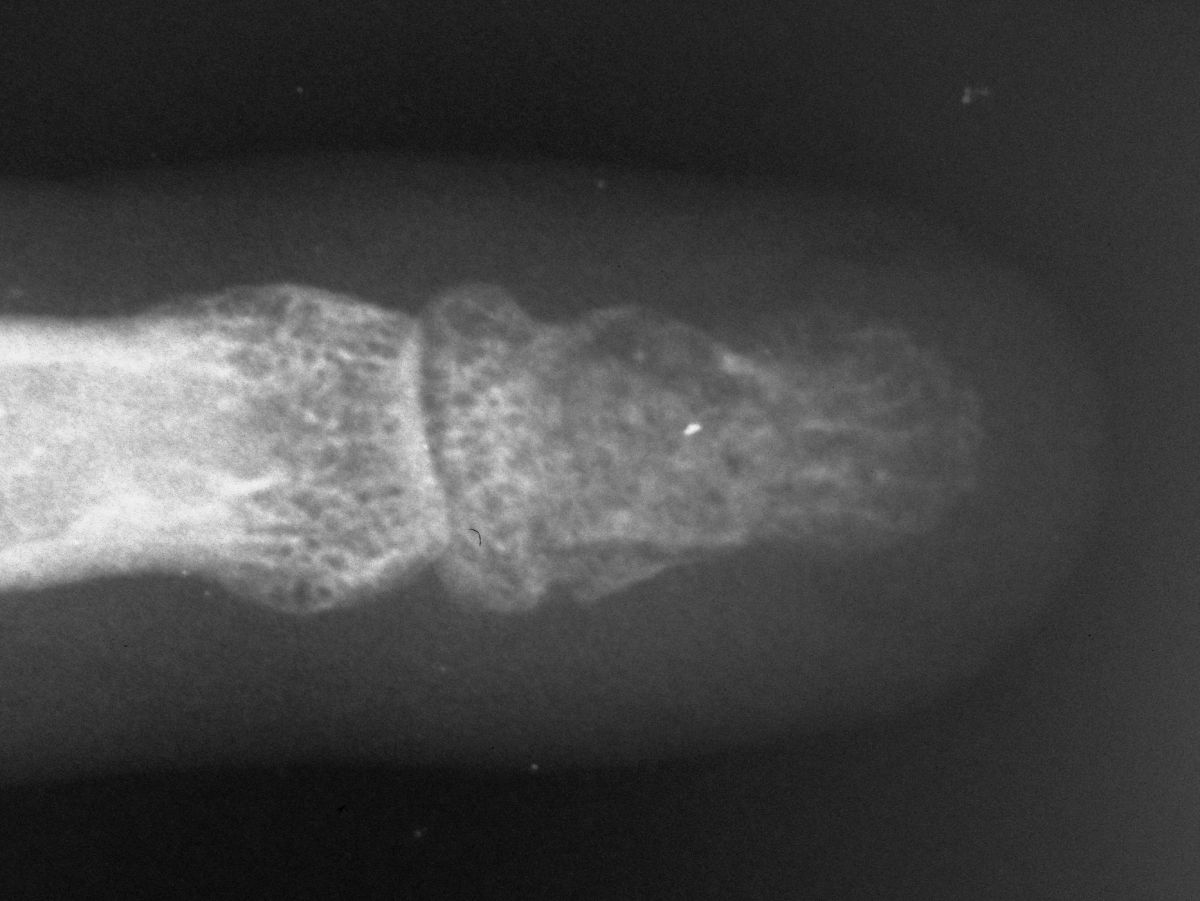

| This was excised through a midline palmar incision. The cavity was debrided with a high speed burr, then packed with cancellous bone. |

| Final result. |